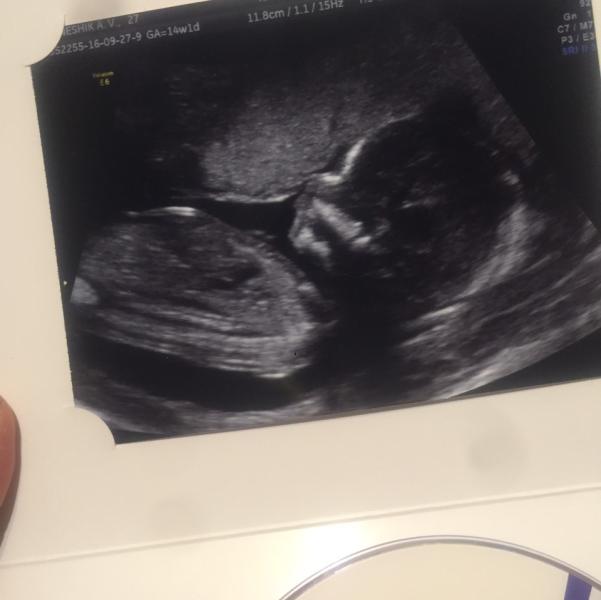

А правда, что, если плод прикреплён к передней стенке, живот начинает быстрее расти? Была на первом скрининге, 14 неделя, живот уже вырисовываться начал

@mamemi, да вот читаю результаты скрининга первого, он по идее в 12-13 недель, я опоздала чуть-чуть, в 14 прибежала